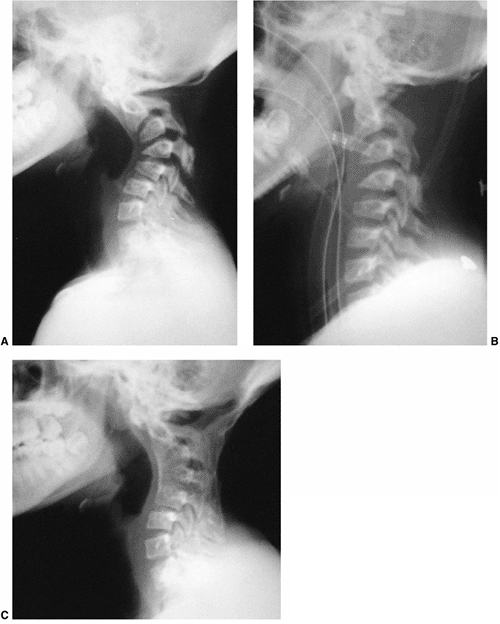

Figure 20.20

Radiographs of a 13-year-old girl treated for a low-grade astrocytoma. She underwent resection of the tumor, a portion of the occiput, and the laminae of C1-C4, followed by radiotherapy at a dose of 5400 cGy. A: A progressive cervical kyphosis developed. Note wedging of the anterior vertebral body. B: Radiograph in halo traction demonstrates partial reduction of the kyphosis. C: Postoperative radiograph after anterior and posterior fusion. |